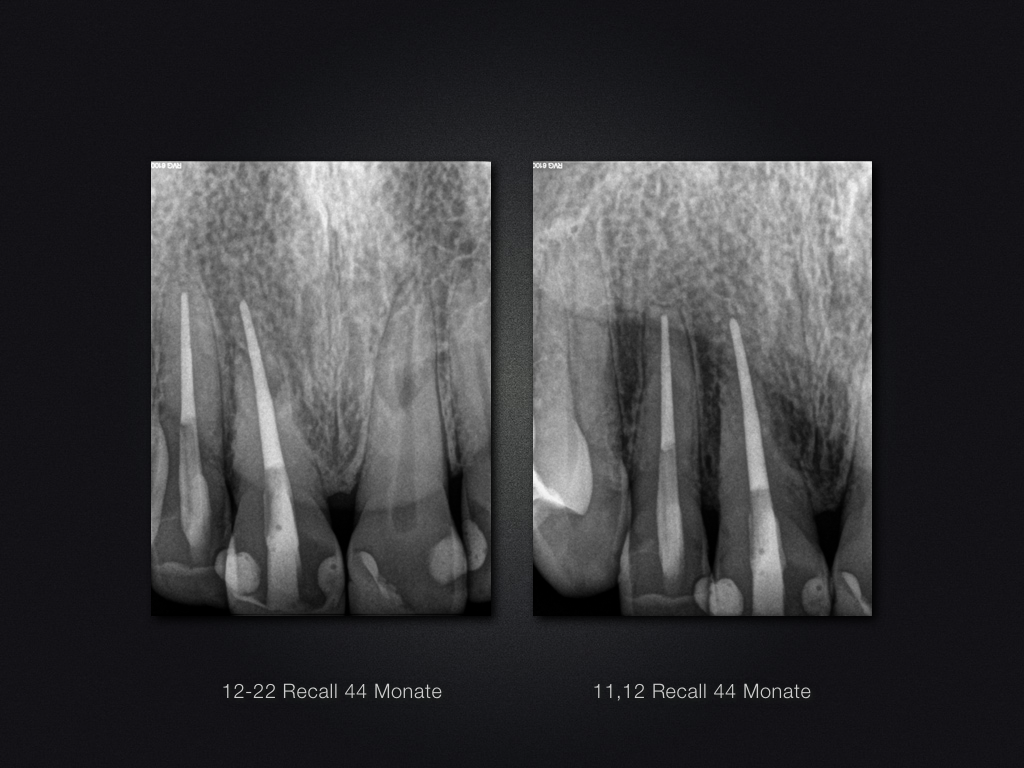

11 21 D Recall.021 Veröffentlicht 22. April 2017 am 1024 × 768 in Traumaspätfolge – knöcherne Ersatzresorption